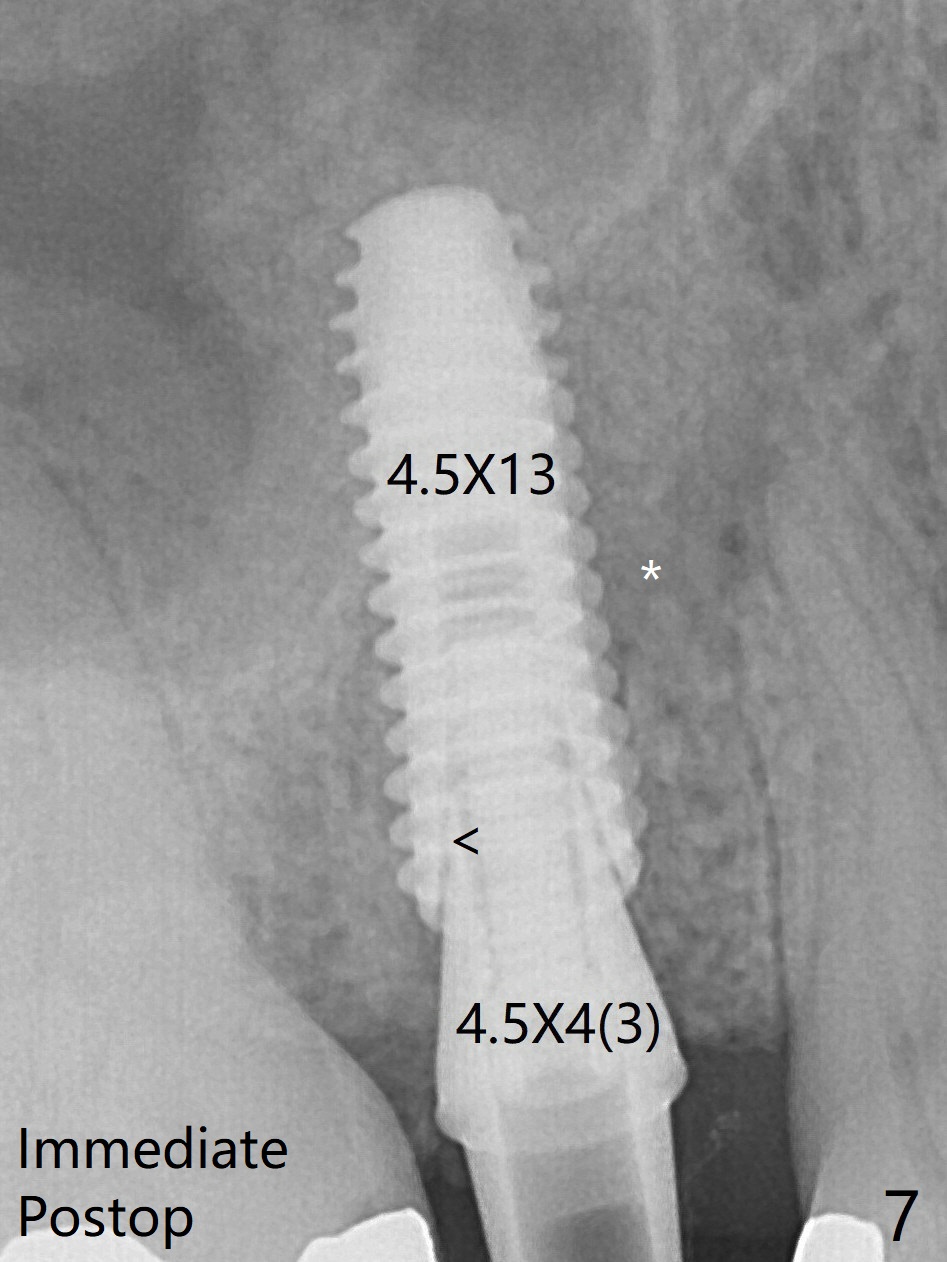

A new abutment with 1 mm longer cuff is seated completely 5.5 months postop (Fig.10 (<: no gap, as compared to Fig.7).